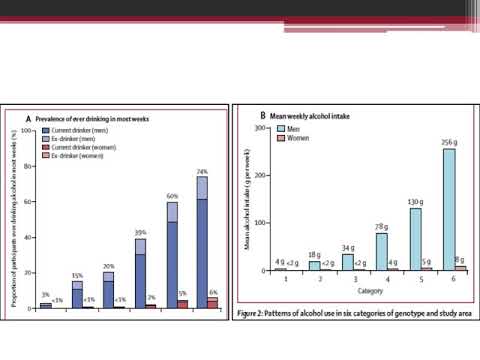

Evidencia genética sobre etiología de las enfermedades vasculares y del alcohol . Un estudio prospectivo de 500 000 hombres y mujeres en China. Dra. Carolina G. Reynoso. Residencia de Cardiología. Hospital C. Argerich Buenos Aires